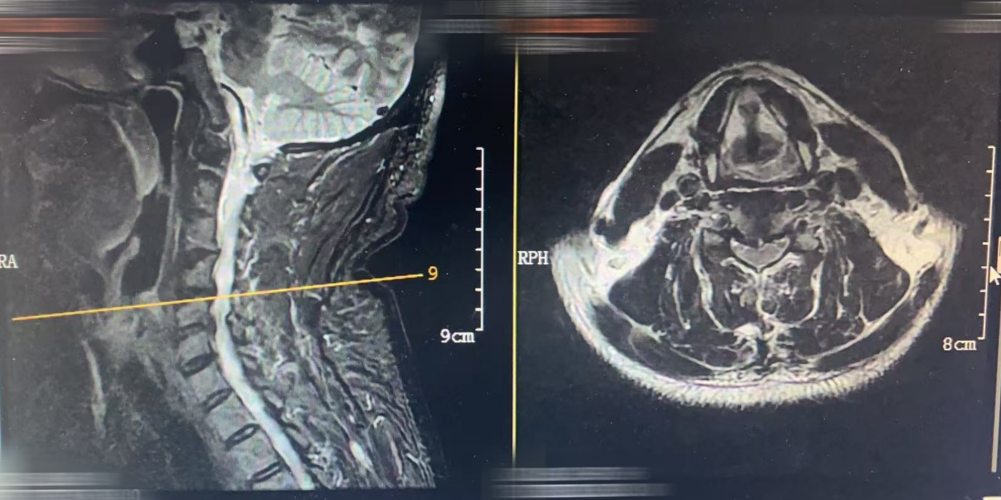

MRI

颈椎生理曲度变直,退行性改变,骨质疏松。

5-6椎间隙上下缘左缘少许终板炎。

3-4椎间膨出并突出;颈4-5椎间盘膨出并右后方突出;颈5-6椎间盘膨出,双侧椎间孔变窄,左侧为主。